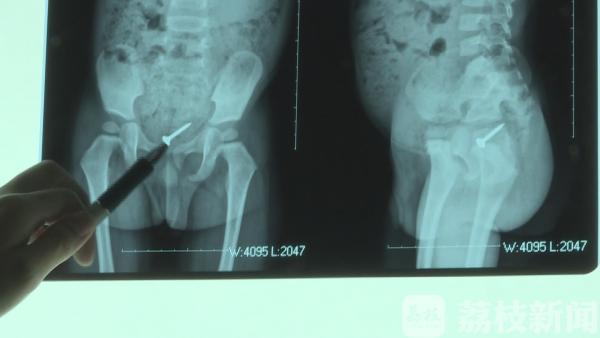

尽管螺丝钉的位置在下移,但毕竟十分尖锐,伴随肠道蠕动,随时有可能发生位置偏移,划破肠壁导致严重的腹膜炎,不及时治疗是致命的。但是为了尽可能避免手术给孩子带来的创伤,医生还是决定继续观察。最后一次复查腹部立位片, 发现这个螺丝钉已经进入盆腔 ,进入了直肠部 ,医生决定用开塞露给他通便 ,通过开塞露灌肠之后 ,很幸运的是,这名小男孩体内的螺丝钉排了出来。